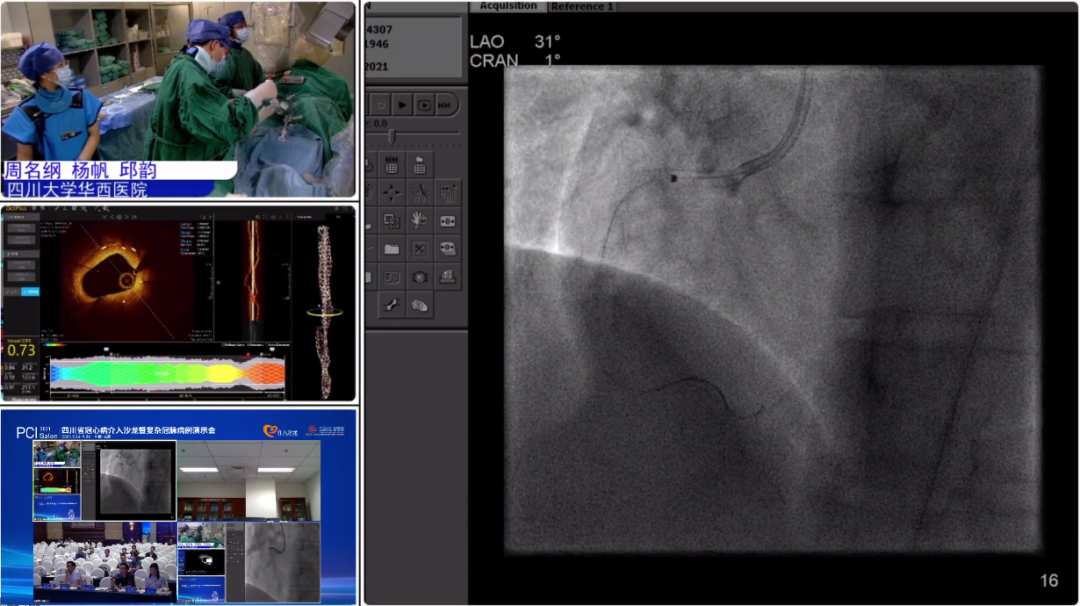

目前,准分子激光冠脉内斑块消蚀术,被行业公认为非常安全有效的冠脉手术治疗方法,也是作为完成复杂冠脉介入手术的一项非常重要的辅助手段。四川大学华西医院贺勇教授团队在会议期间演示了一例准分子激光冠脉消蚀术。

该患者为75岁男性,10 +月前因“体检发现冠心病”入院,无明显肢体缺血表现,2020-11-02于我院行冠脉造影及支架植入术:左冠状动脉-回旋支-前降支(PTCA)(支架SYNERGY3.0mm*16mm*1)。目前患者无不适,主诉为求冠脉造影复查入住我科,入院查体无明显特殊。

冠脉造影:右冠状动脉支架内膜增生,开口处狭窄最重约80%,中远段狭窄最重约60%

结论:原支架内膜增生,开口处中度狭窄、支架严重膨胀不良。

手术过程:

术前OCT显示支架狭窄处短段直径为1.3mm,团队讨论后决定使用1.4mmELCA导管,在激光销蚀前,先用1.5mm的球囊进行了一次预扩张,再用准分子激光以参数为45mj/40Hz进行消蚀。由于激光的作用范围能使管腔直径1.5倍范围内的组织也得到松解软化。因此选用1.4 mmELCA导管,是希望通过激光消蚀与软化组织对支架外的组织产生松解软化作用,获得更大的管腔。但1.4mm激光导管在最狭窄处通过性不好,2.5mm高压球囊也不能将狭窄处管腔扩大到1.5mm,遂换0.9mmELCA导管继续进行激光消蚀术。0.9mmELCA导管通过性好,通过参数为60mj/60Hz以及60mj/70Hz进行两次激光消蚀,在激光的消蚀和松解软化斑块作用下,顺利地使用2.5mm高压球囊扩张成功,手术圆满完成!